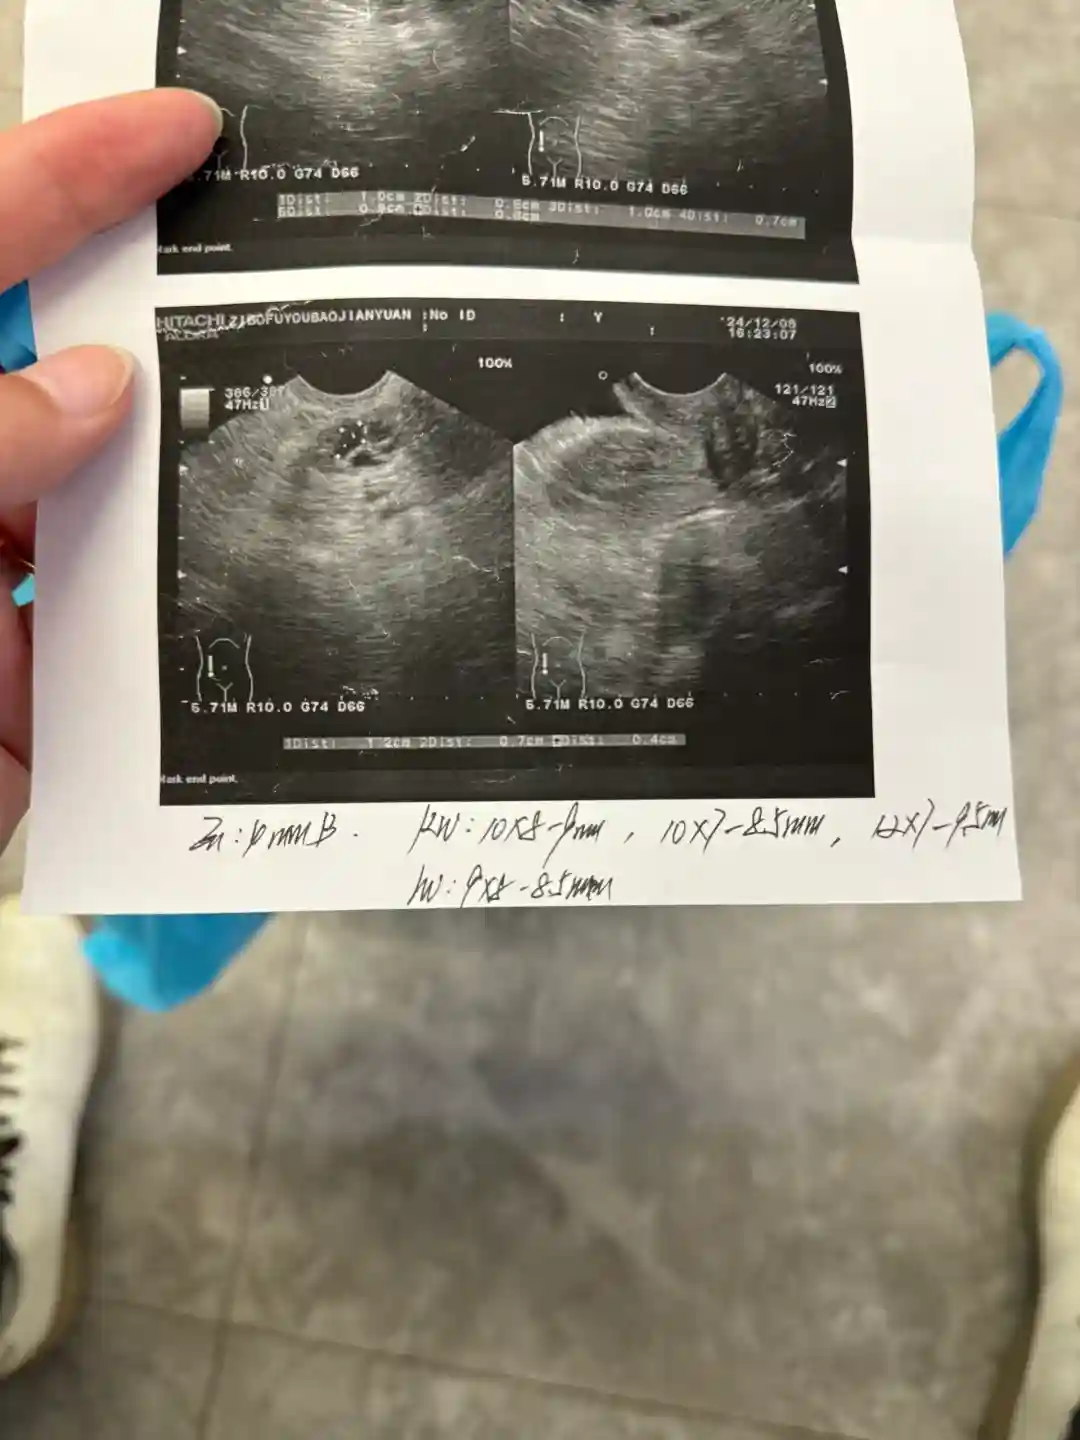

12.8Day10 内膜4 右12×7×9.5 10×8×9 10×7×8.5 左9×8×8.5 75尿促一针

12.12Day14 内膜8 右20×17×18.5 左11×10×10.5 75尿促一针#备孕日记 #备孕 #接一切好孕 #多囊备孕 #接好孕 #多囊促排